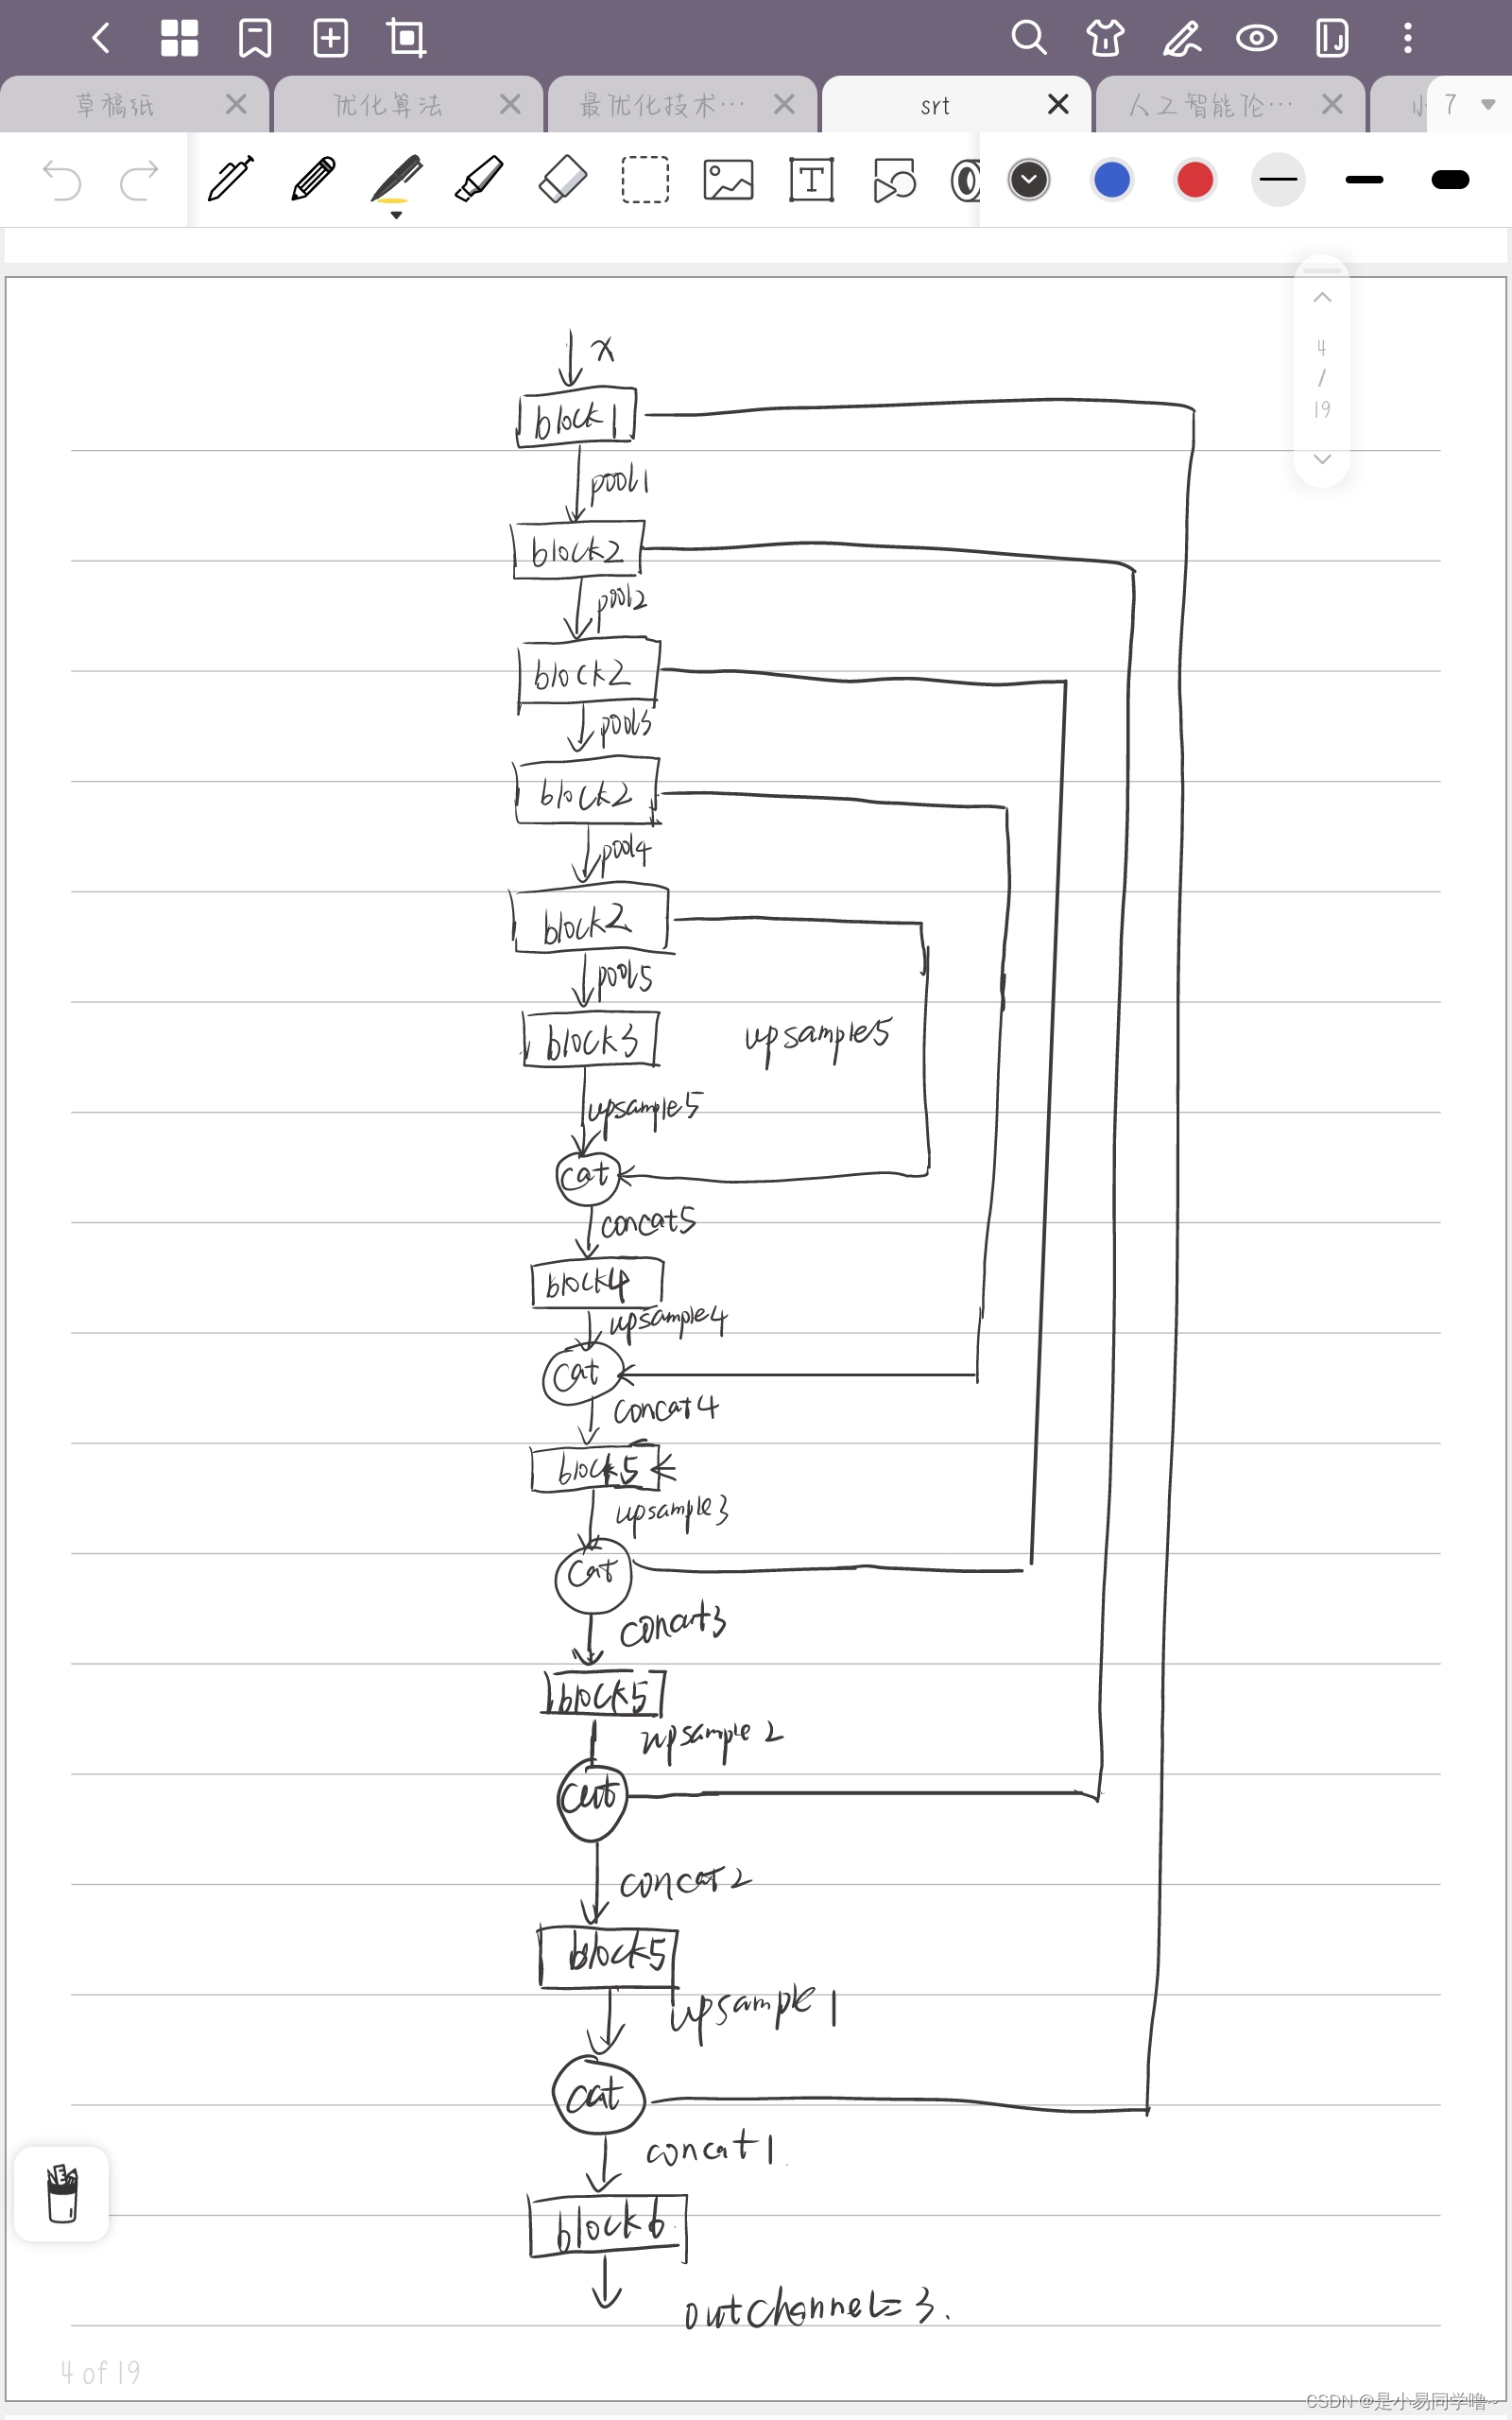

N2N的网络没有改动,如下为网络示意图(只在最初的输入通道处有改动)